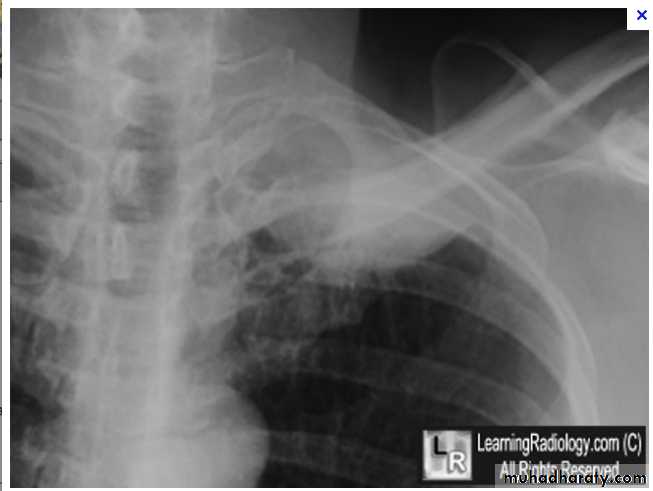

Massive pleural effusion with mediastinal shift to the left.

(A) Chest radiograph(B) CT coronal reconstruction. A massive effusion displaces the mediastinum to the left. CT shows the important pleural effusion together with the enhanced atelectatic left lung.

Note also the depression of the right hemidiaphragm (arrows).